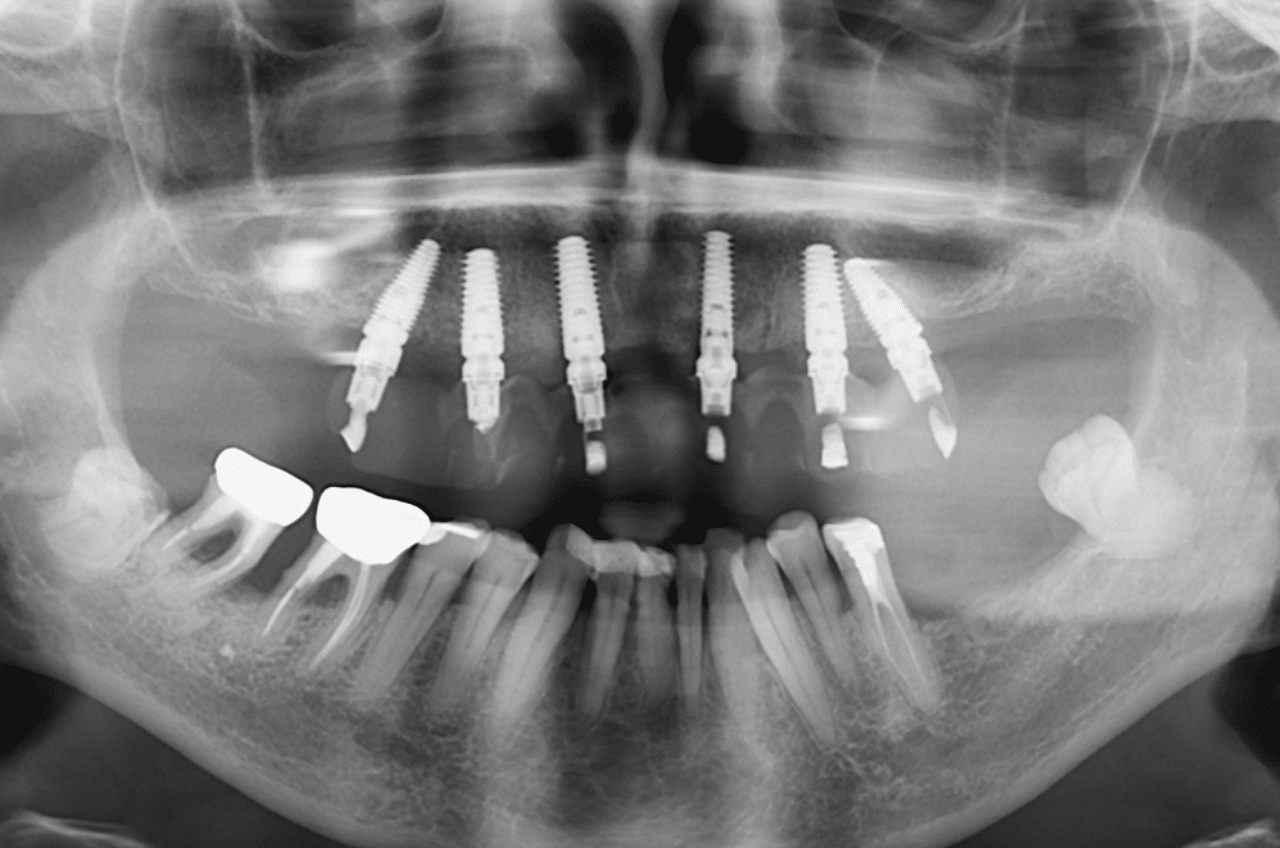

Radio de contrôle post-opératoire (les alvéoles ont été comblées par os autogène et BioOs) :

Notez que l’axe des implants distaux a permis d’éviter les sinus pour une simplification du protocole chirurgical